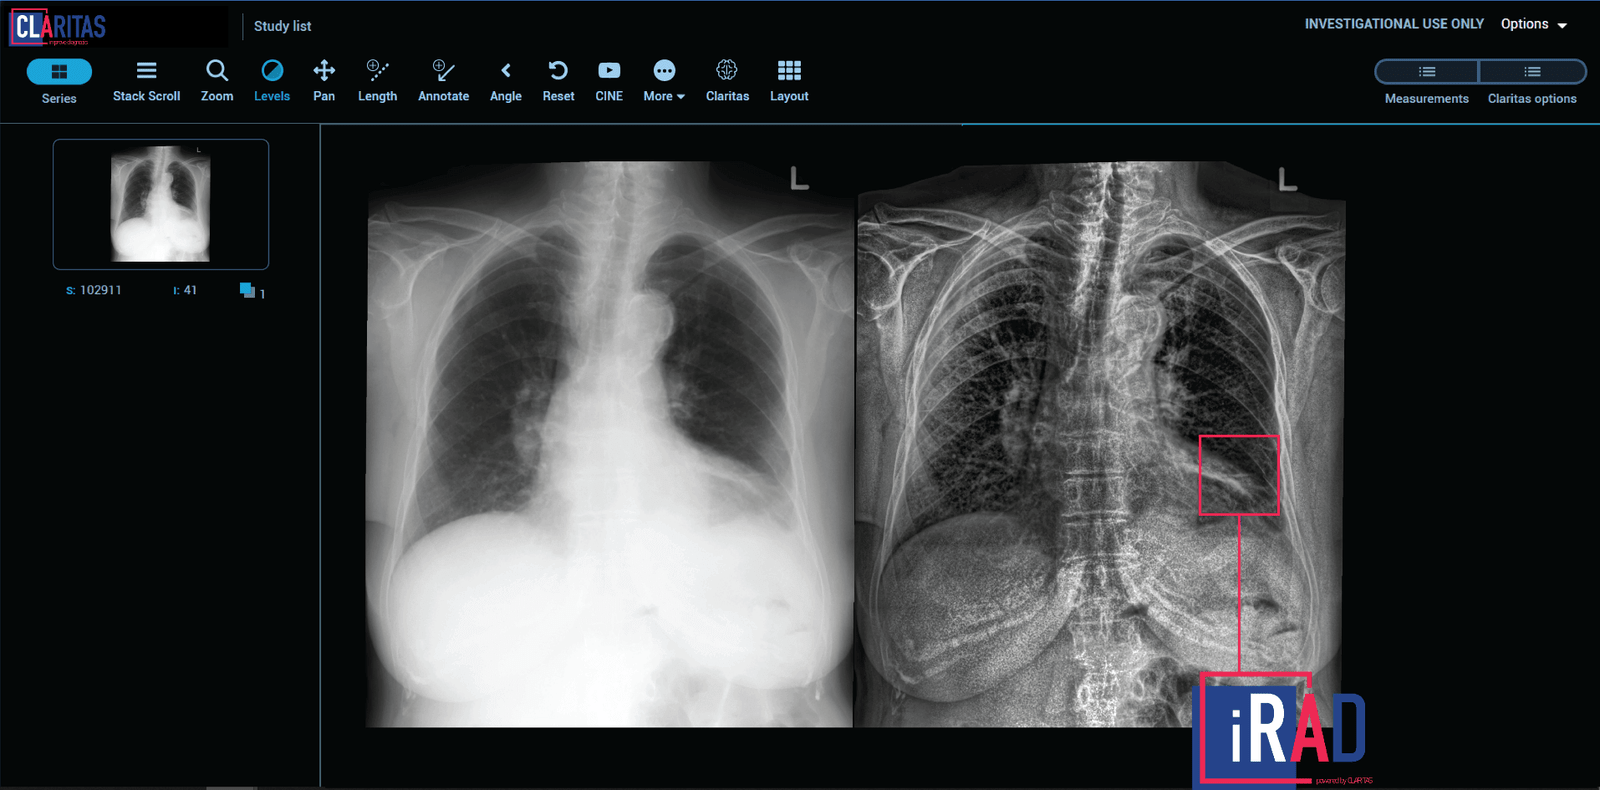

Image Caption: Claritas iRAD Platform

To overcome the shortcomings of the existing technology available, a team of imaging specialists, scientists and mathematicians at Claritas HealthTech, have developed Claritas iRAD and engineered an image enhancement process that preserves the finest details by individually enhancing each pixel to produce an image of high precision. Whether unclear due to radiation, low light or tissue absorption, the unique methods at Claritas HealthTech greatly improves clarity, without distorting, exaggerating or compromising the details of the original image.

Claritas iRAD can be seamlessly integrated into any of the existing radiology platforms, such as PACS (Picture archiving and communications systems) Viewer, to support better workflow. Additionally, as the platform is accessed through the Cloud, Claritas HealthTech provides fast image processing at a user-friendly level, with no need for lengthy and complex training, even for first-time users.